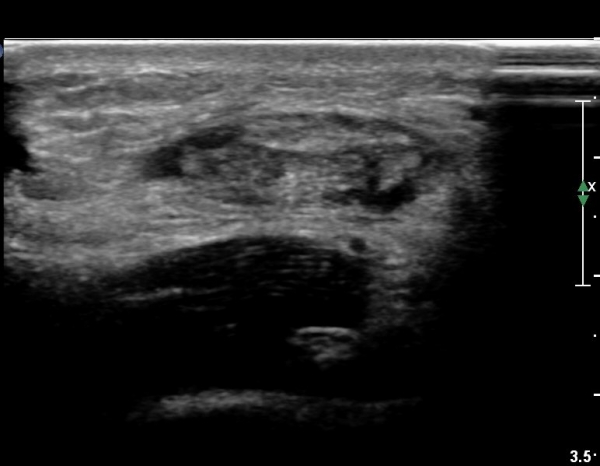

ºñº¹±Ù Á¾´Ü¸é°Ë»ç¿¡¼ ƯÀÌ ¼Ò°ßÀ» º¸ÀÌÁö ¾ÊÀ½(»çÁø 1).

¾ÆÅ³·¹½º°Ç Á¾´Ü¸é°Ë»ç¿¡¼ ¾ÆÅ³·¹½º°Ç Àú¿¡ÄÚ ºÎÁ¾, ¿¬°á¼º ¼Ò½Ç, °ÇÁÖÀ§ ¼ö¾×Àú·ù ¼Ò°ßÀ» º¸ÀÓ(»çÁø 2, 3, 4, 5).